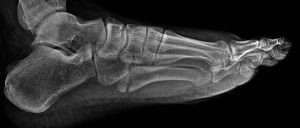

第4、5跖骨與跟骨和骰骨構成外側縱弓,5根跖骨基底部組成足的橫弓。第5跖骨活動範圍最廣,其與第4跖骨只有較松的韌帶相連。此處有3個關節:骰骨與第4跖骨相關節,骰骨和第5跖骨相關節,第4、5跖骨間關節。數支骨骺和乾骺端動脈提供基底部和粗隆部的血運,但只有一根營養動脈從內側皮質進入骨幹的近中1/3處為骨幹提供血運,此根營養動脈只發出一個縱向的髓內分支供應骨幹和粗隆部交界處血運,骨折很容易造成其損傷,所以此處很容易發生骨延遲癒合或不癒合。